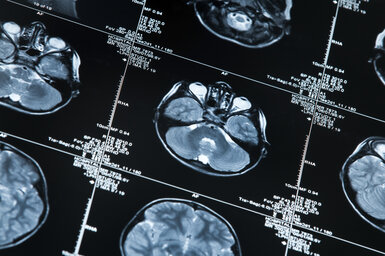

EMPIR project developing non-invasive techniques for diseases such as Alzheimer’s and Parkinson’s has a number of successful outcomes more

Project research is developing quantitative MRI analysis for more objective disease diagnostics more